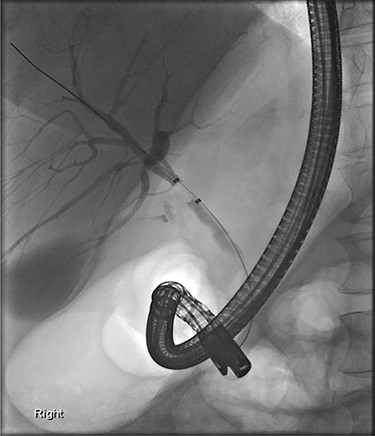

Computerized tomography demonstrated an enhancing soft tissue thickening in the gastric pylorus with soft tissue extension into the left lobe of the liver, invasion of the left intrahepatic bile ducts with obstruction and dilatation of the left sided intra- and extrahepatic biliary tract (Fig. 1). Oesophagogastroduodenoscopy (OGD) showed a pre-pyloric fistula (Fig. 2).

Further examination led to a diagnosis of DCBD with a separate left intra- and extrahepatic bile duct with ectopic drainage into the stomach. Magnetic resonance cholangiopancreatography (MRCP) revealed marked left intrahepatic duct (IHD) dilatation. The left IHDs were draining via an aberrant extra-hepatic bile duct into the pre-pyloric region. The left and right hepatic ducts did not communicate. It also demonstrated pancreatic divisum and multiple side branch intra-ductal papillary mucinous neoplasms (IPMN) (Fig. 3). Endoscopic retrograde cholangiopancreatography (ERCP) confirmed the MRCP findings but also revealed an intraluminal-filling defect in the left IHD (Figs 4 and 5).

ERCP: cannulation via the major papilla orifice into the CBD draining the right IHDs. There was no communication between the ACBD and the right IHDs.

ERCP: cannulation via the pre-pyloric fistula opening. Contrast outlining the ACBD and the left IHDs.